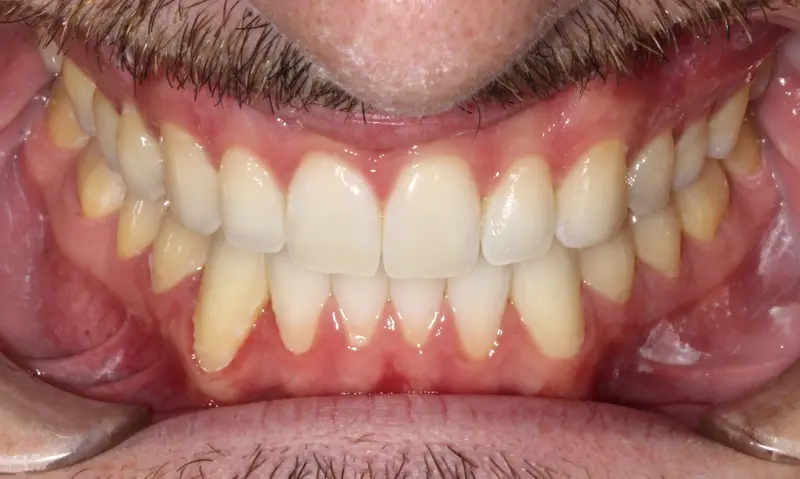

After treatment: Vertical Control & Intrusion

After

Before treatment: Vertical Control & Intrusion

Before

Deep bite with over-erupted upper central incisors. The patient presented with a "Gummy Smile" and uneven gingival margins, where the front teeth sat too low relative to the upper lip.

We utilized Temporary Anchorage Devices (TADs) to apply pure intrusive forces. By anchoring to the bone, we lifted the anterior teeth and gum line upwards (Intrusion) to reduce the gummy display and level the smile arc without jaw surgery.